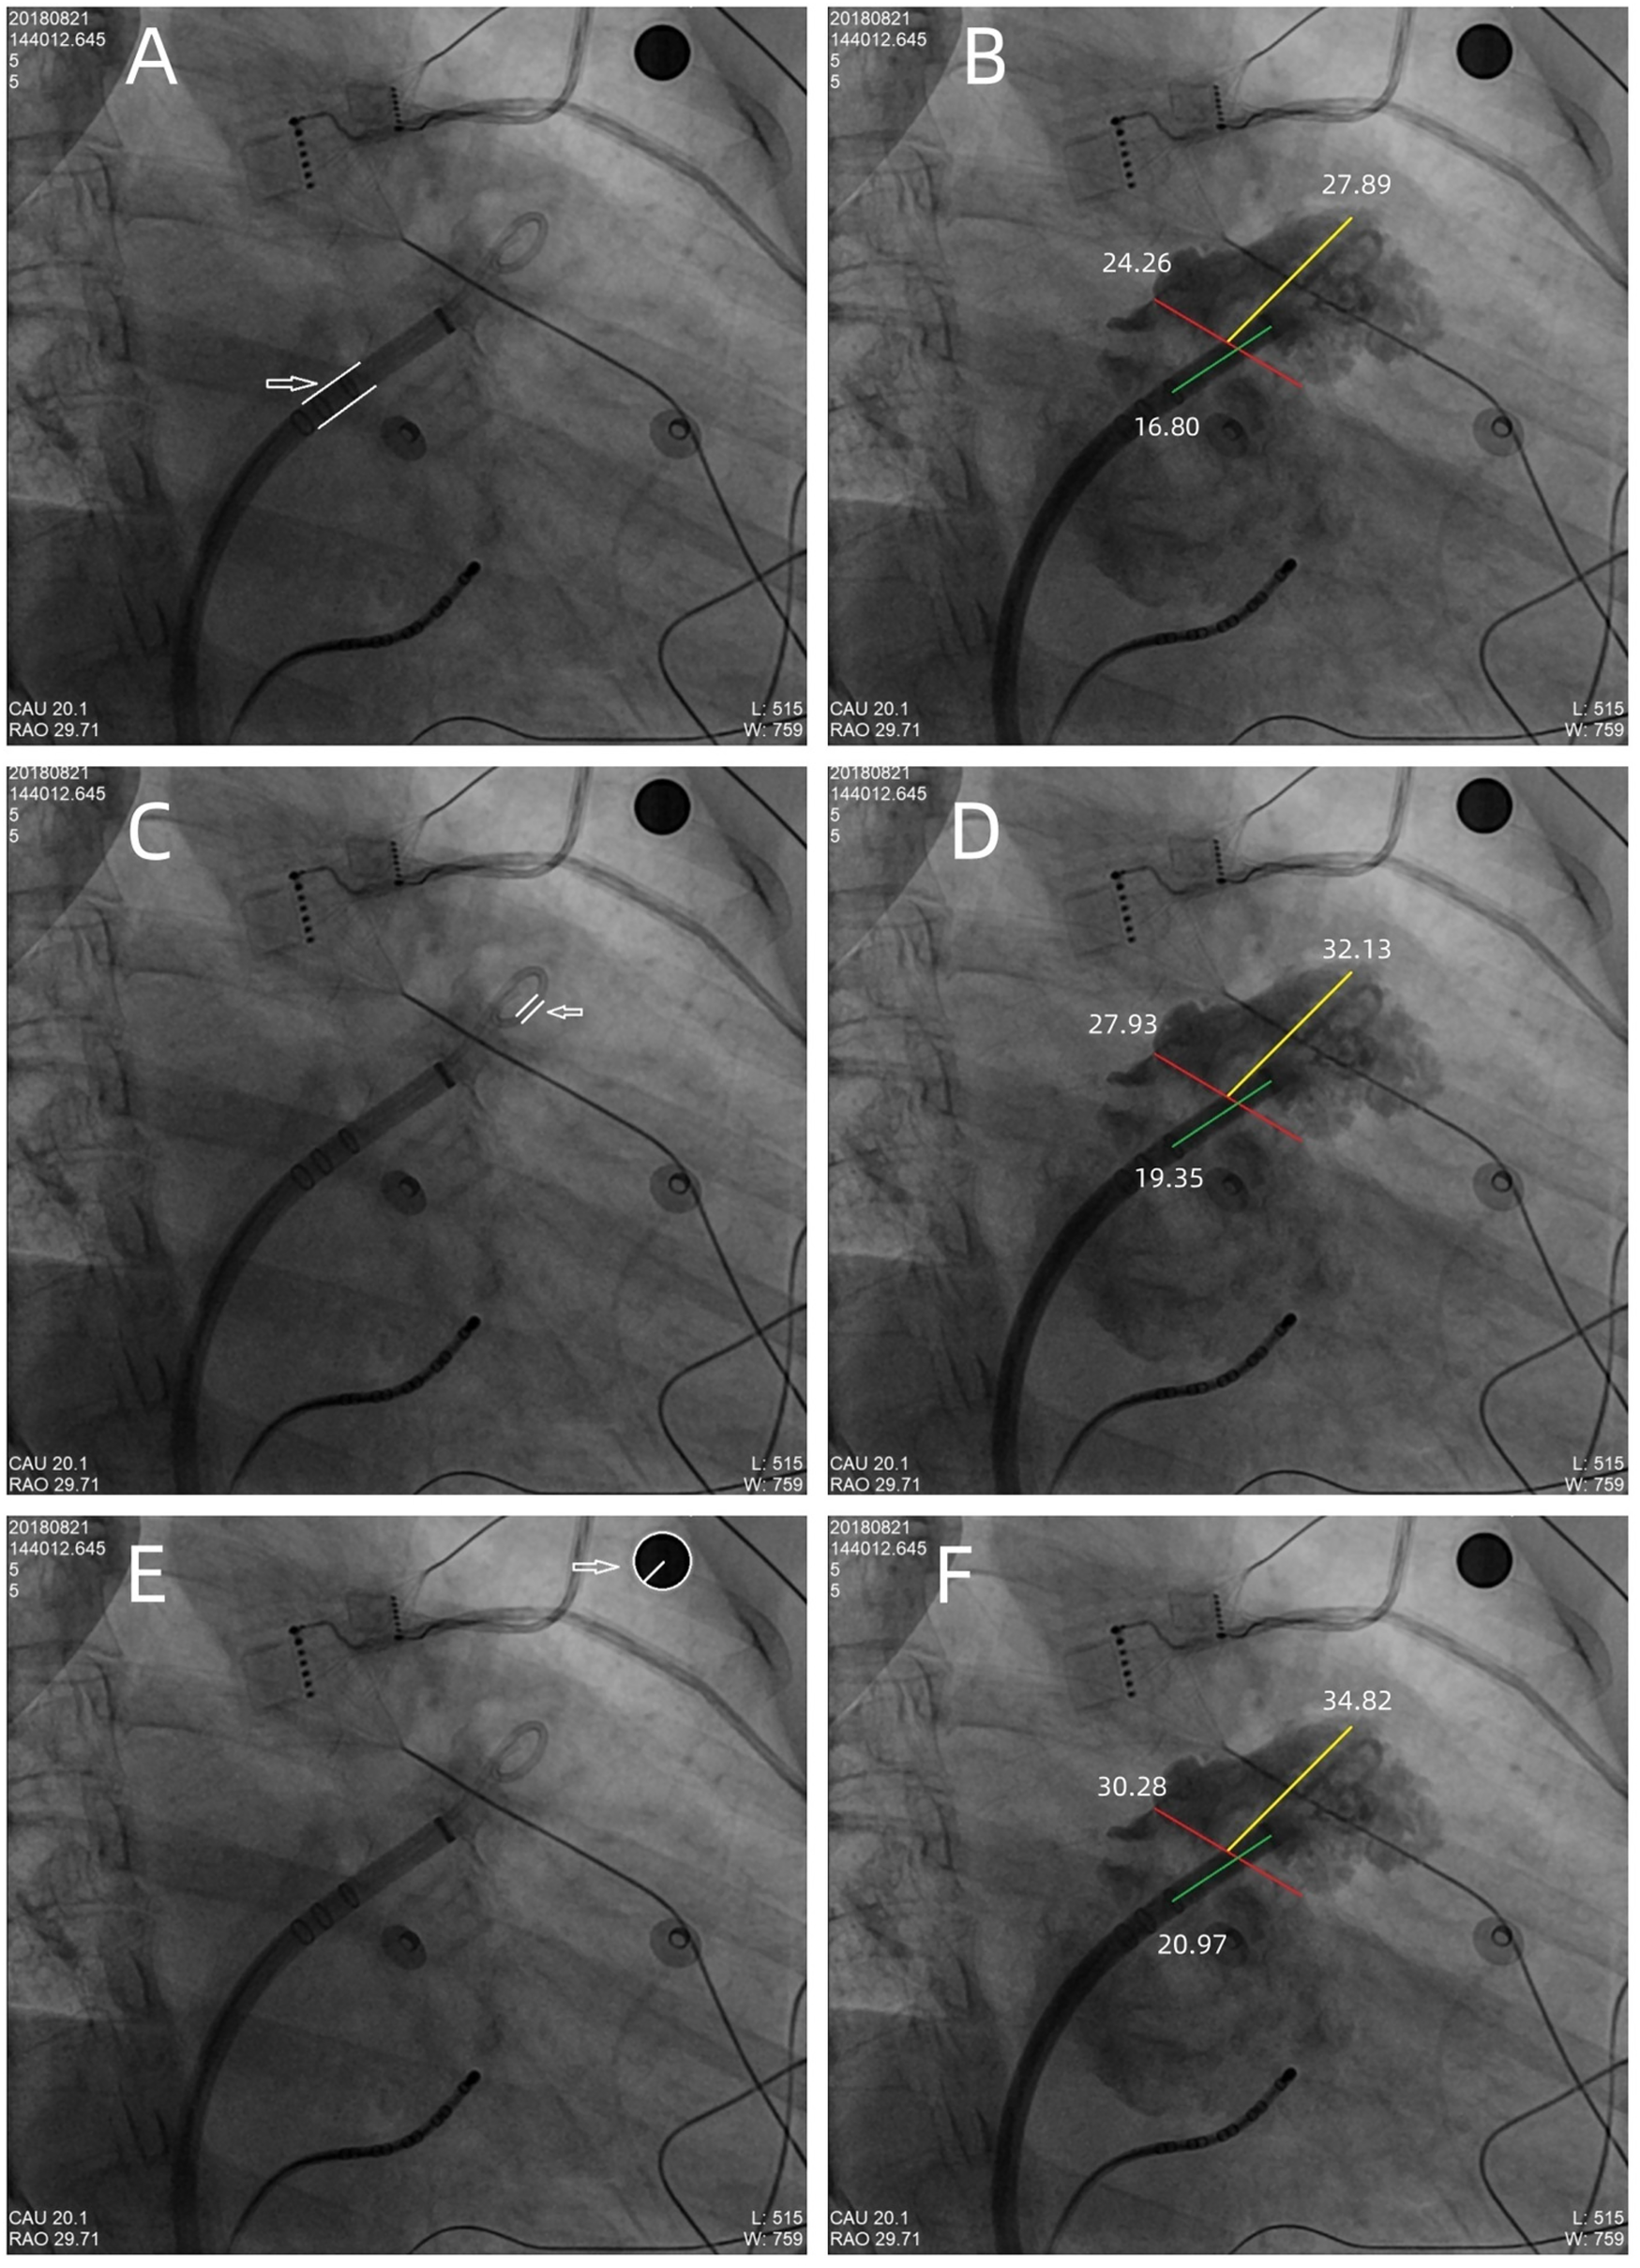

Figure 2

The maximum LAA ostium diameter, maximum LAA depth, and 1st sheath marker band length were measured under x-ray fluoroscopy, using the delivery sheath, pigtail sheath, and steel ball as references, respectively. (A,B) The double white lines pointed by the white arrow showed the 12Fr inner diameter delivery sheath (4 mm in diameter) as reference scale, the red line showed the measurement of maximum LAA ostium diameter (24.26 mm), the yellow line showed the measurement of maximum LAA depth (27.89 mm), and the green line showed the measurement of 1st sheath marker band length (16.80 mm). Similarly, in (C,D), the double white lines showed the 5Fr delivery sheath (1.67 mm in diameter) as reference scale, the red line, yellow line, and the green line showed the measurement of maximum LAA ostium diameter (27.93 mm), maximum LAA depth (32.13 mm), and 1st sheath marker band length (19.35 mm), respectively. (E,F) The white arrow showed the steel ball (10 mm in diameter) as reference scale, the red line, yellow line, and green line showed the measurement of maximum LAA ostium diameter (30.28 mm), maximum LAA depth (34.82 mm), and 1st sheath marker band length (20.97 mm), respectively. In this case, a 33 mm Watchman device was successfully implanted with satisfactory results.